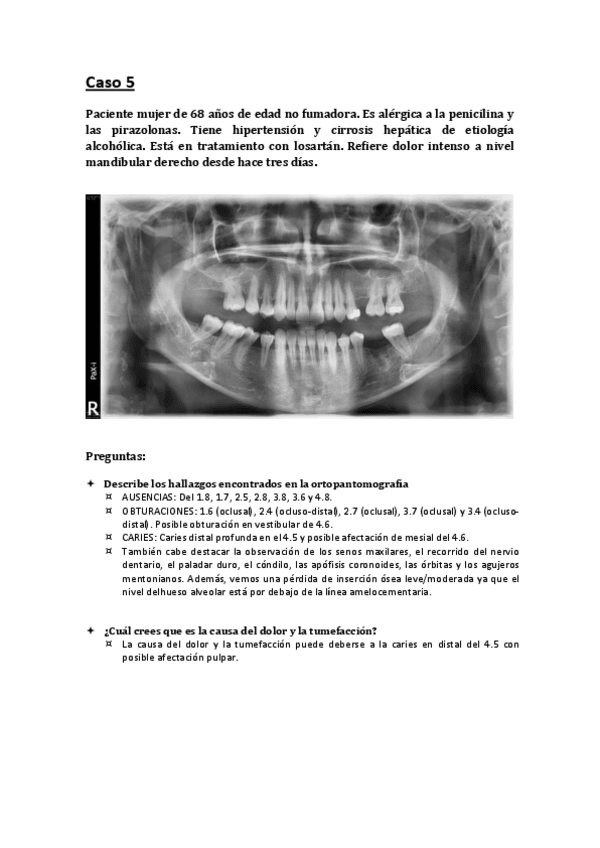

Caso-5.pdf